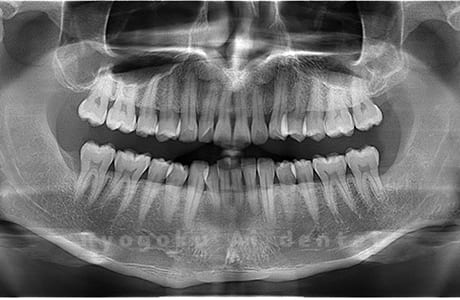

水平埋伏の親知らず

歯茎の中で完全に横に生えてしまうタイプです。

この親知らずを水平埋伏智歯と言います。このタイプはほとんどが下顎のケースです。真横に生えているので抜歯の際は難易度が高く2~3つに砕いて分けて抜歯をします。